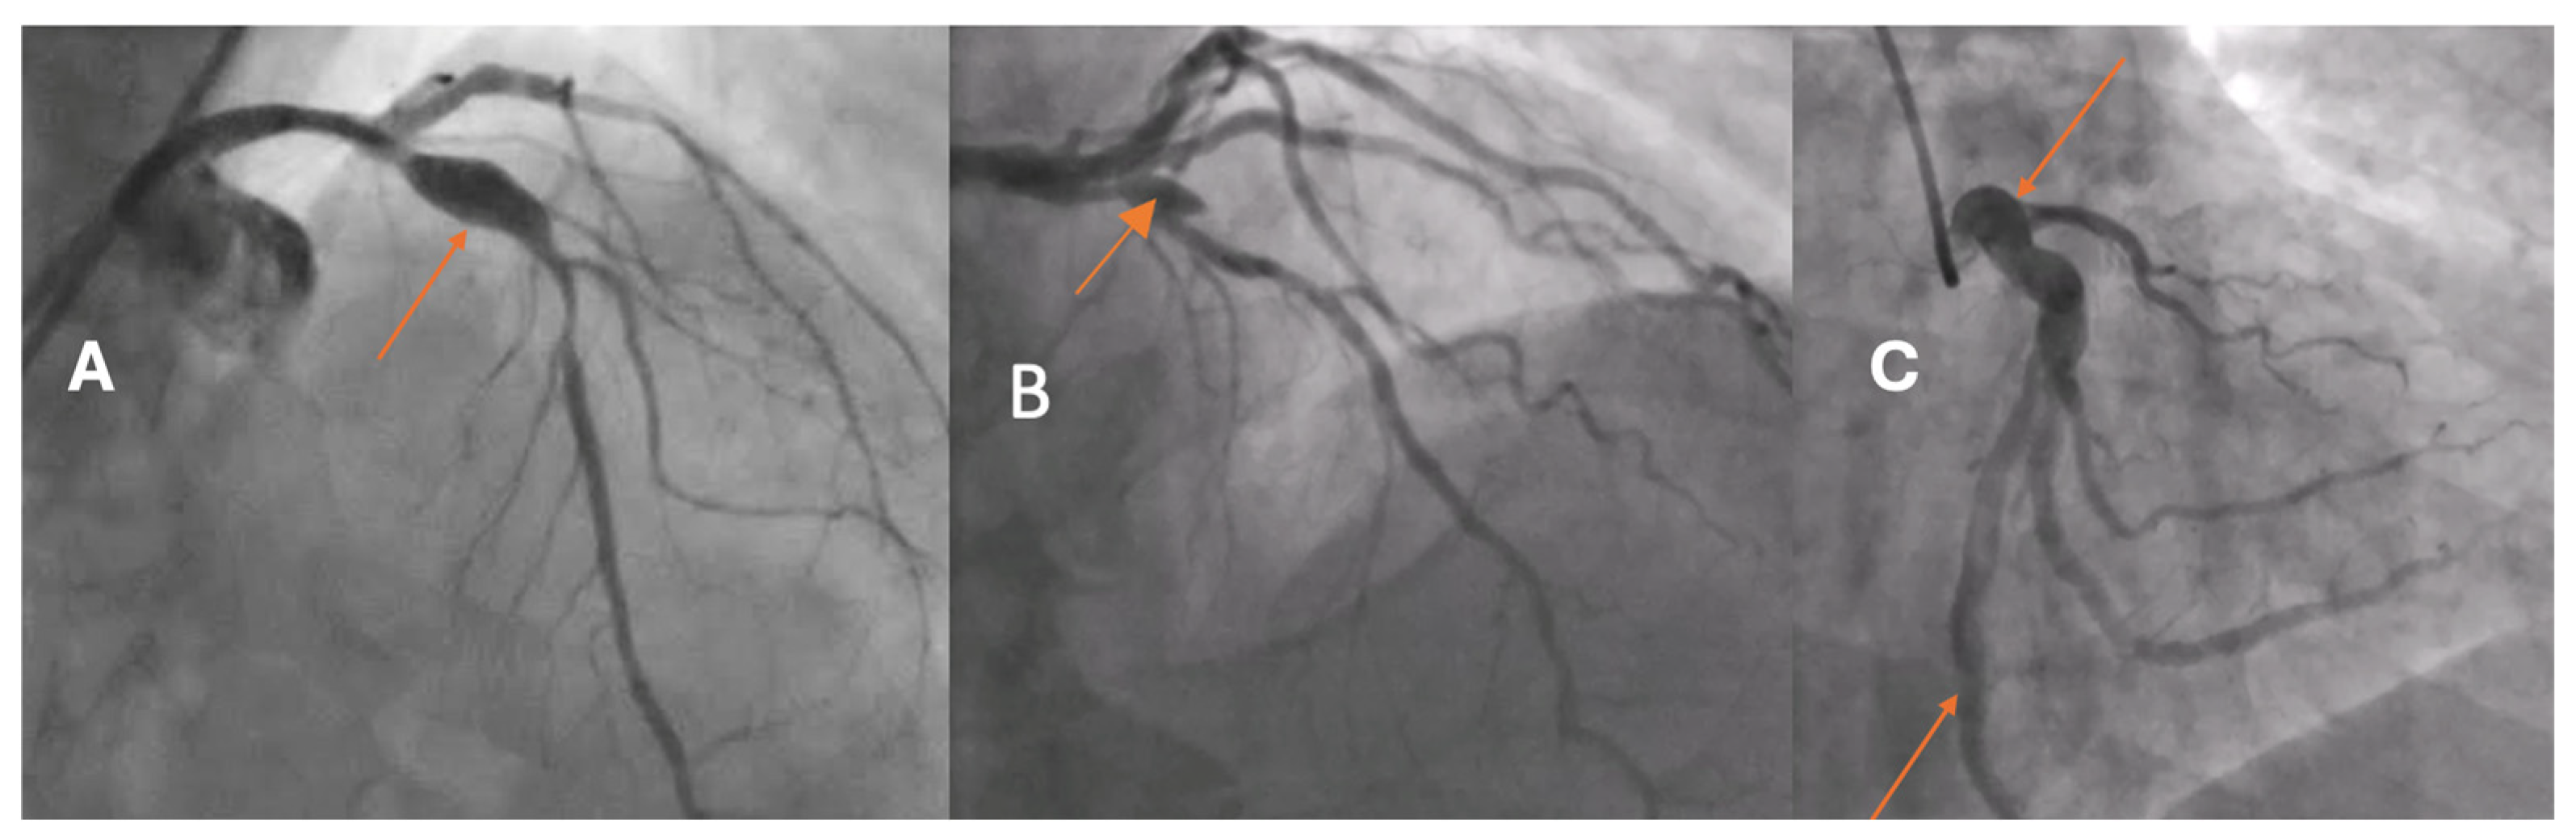

5]. Based on the extent of arterial involvement and the relationship between the transverse and longitudinal dimensions, two morphological types are distinguished: coronary artery ectasia (CAE), defined as a diffuse dilatation involving at least one-third of the vessel length, and coronary artery aneurysm (CAA), a focal dilatation that may be saccular or fusiform (

Figure 1). In both CAE and CAA, the dilated segment exceeds the reference vessel diameter by ≥1.5-fold.

CAAE encompasses two phenotypes: CAE, defined as a diffuse dilatation of a coronary artery to ≥1.5 times the diameter of an adjacent normal reference segment that involves at least one-third of the vessel length, and CAA, defined as a focal dilatation of a coronary artery to ≥1.5 times the diameter of the nearest normal segment (

Figure 1). CAA is morphologically classified as saccular when the transverse diameter exceeds the longitudinal dimension and as fusiform when the longitudinal dimension exceeds the transverse diameter with circumferential, spindle-shaped involvement of the vessel. A “giant” CAA is commonly designated when the diameter exceeds four times the reference caliber or is greater than 8 mm.

The majority of aneurysmal or ectatic lesions were located in the left anterior descending artery (LAD) (42.9%), followed by the right coronary artery (RCA) (28.6%) and the left circumflex artery (LCx) (9.5%). Only one case (4.8%) involved the left main coronary artery (LMCA), while no aneurysms were identified in the diagonal, intermediate, or marginal branches. Baseline angiographic characteristic is presented in

Table 2. Regarding morphology, CAE was the predominant form, observed in 61.9% of patients, whereas fusiform aneurysms accounted for 28.6% and saccular aneurysms for 9.5%. The median maximum lumen diameter was 5.3 mm (IQR 4.7–5.9), and the median lesion length was 10.0 mm (IQR 8.1–12.5). No giant aneurysms were detected in the study population.

These findings indicate that aneurysmal and ectatic changes most frequently affect the LAD and predominantly manifest as diffuse ectatic remodeling rather than discrete saccular dilatations, supporting the concept of progressive vessel wall weakening and outward remodeling along the major coronary branches.